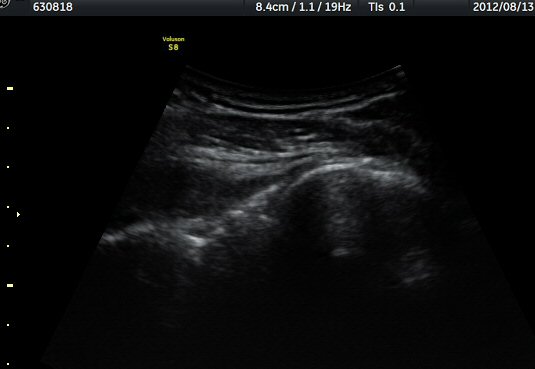

ÈíÀÎ 50ÀÏ ÈÄ ÃÊÀ½ÆÄ°Ë»ç¿¡¼­ ³¶Á¾ Å©±â °¨¼Ò°¡ ¶Ñ·ÈÇÏ´Ù(±×¸² 9, 10).